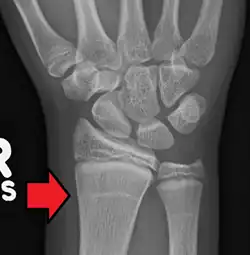

Growth arrest lines in a child with an underlying bone disease

Growth arrest lines, also known as Harris lines, are lines of increased bone density that represent the position of the growth plate at the time of insult to the organism and formed on long bones due to growth arrest. They are only visible by radiograph or in cross-section. The age at which the lines were formed can be estimated from a radiograph. Harris lines are often discussed as a result of juvenile malnutrition, disease or trauma. Other studies suggest a reconsideration of Harris lines as more of a result of normal growth and growth spurts, rather than a pure outcome of nutritional or pathologic stress.[1] The lines are named after Henry Albert Harris (1886–1968), professor of anatomy at the University of Cambridge.[2]